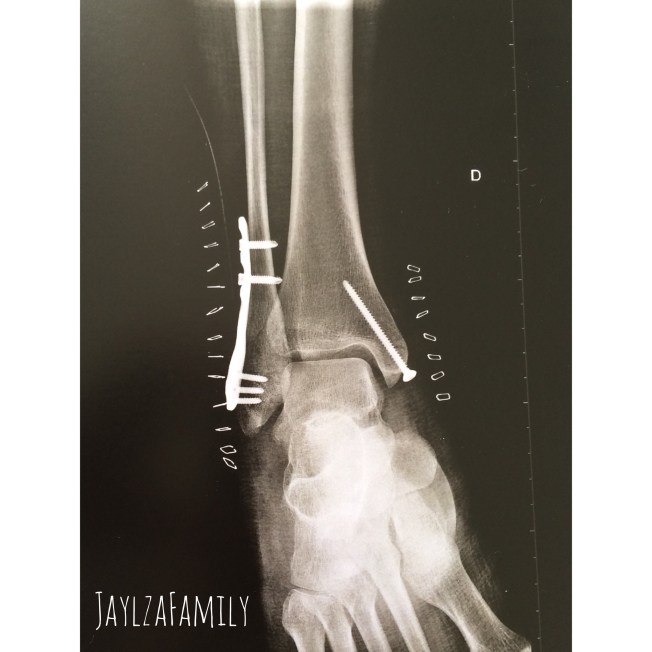

(Dehors)

(Dedans)